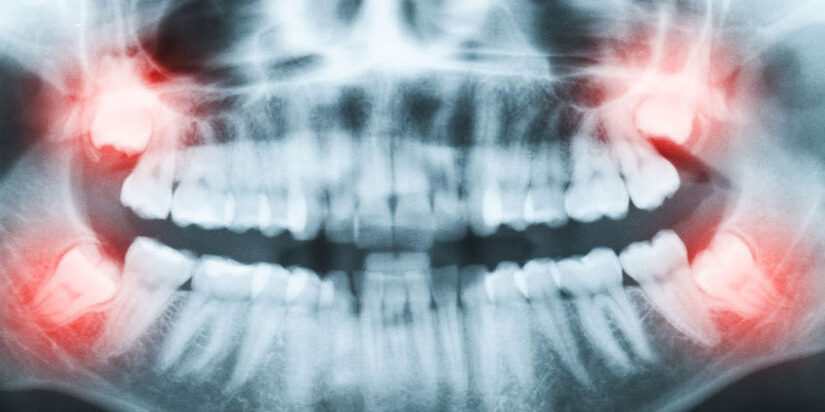

Whether your surgical needs are extraction of wisdom teeth, an implant to replace a missing tooth, or anything in between, we promise to provide you with exceptional care. We strive to perform all our procedures with a gentle touch for your comfort. Your oral health is our priority, and we will give you something to smile about. Our goal is to assist each patient in achieving and maintaining long term oral health and a beautiful smile.